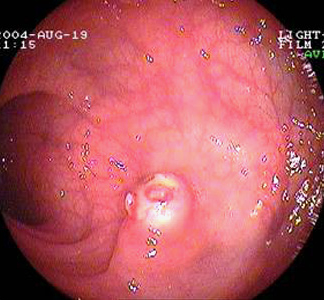

Polypen sind flächige oder pilzförmige Geschwülste (Tumore) der Dickdarmschleimhaut, die in die Darmlichtung hineinragen. Sie sind meist gutartig und gehen vom Drüsengewebe der Darmschleimhaut aus (Adenome). Aus ihnen entwickelt sich jedoch die Mehrzahl aller Dickdarmkrebse (Kolonkarzinome). Mehr als 50% der Dickdarmpolypen befinden sich im Mastdarm.

Da die Polypen oft keine Beschwerden verursachen werden sie oft rein zufällig bei einer Spiegelung des Dickdarms (Koloskopie) entdeckt.

Polypen werden meistens endoskopisch mithilfe einer Zange oder Schlinge abgetragen und dann feingeweblich (histologisch) untersucht. Bei grösseren Polypen, besonders wenn sie flach und breitbasig der Darmschleimhaut aufliegen, ist eine Operation (Darmresektion) durchzuführen.